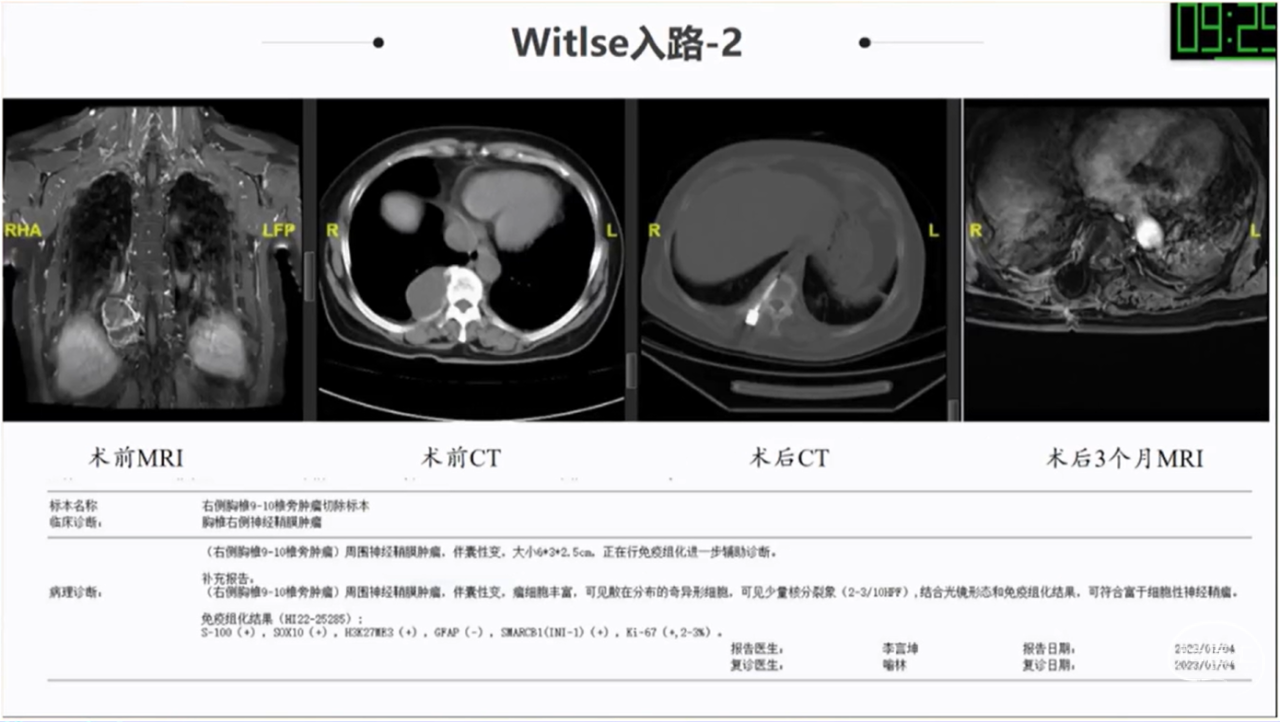

椎旁肿瘤种类多样,手术切除是主要的治疗方法;血供一般,病灶内切除减容,为肿瘤的全部切除提供有利条件;Witlse入路治疗椎旁巨大肿瘤优势明显;椎体破坏、血管侵犯、胸膜下的病例尽量选用经胸入路或者联合入路。

· Witlse入路治疗椎旁巨大肿瘤优势明显